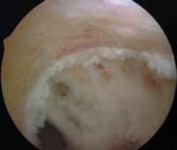

5. In revision ACL reconstruction, the notch often is overgrown and narrow, likely as a result of the previous ACL reconstruction (

TECH FIG 1A

).

1. A notchplasty is completed with use of a 5.5-mm burr, starting at the anterior opening of the notch if necessary.

2. The location of the previous femoral tunnel is noted.

3. Notchplasty is carried back to the posterior wall as needed. A small, curved curette may be used to inspect the back of the notch. A thin white strip of periosteum usually identifies the posterior wall (

TECH

### FIG 1B). Careful attention to localizing the posterior wall is critical, especially because the sides and roof of the notch often are irregular owing to the previous surgery.

TECH FIG 1 • A. Significant overgrowth of the notch noted at the time of revision anterior cruciate ligament (ACL) reconstruction. B. A thin layer of periosteum is easily visualized at the posterior wall of the notch. C. Note the anterior placement of the femoral tunnel interference screw used during the primary ACL reconstruction. The femoral tunnel for the revision can be placed at the appropriate location without removing the interference screw used in the primary procedure. D. The new femoral tunnel and interference screw are placed in the appropriate location without compromise from the screw used in the index procedure. E. View of femoral notch after placement of femoral tunnel and interference screw via anteromedial portal. This allows divergence of the old and new femoral tunnels.